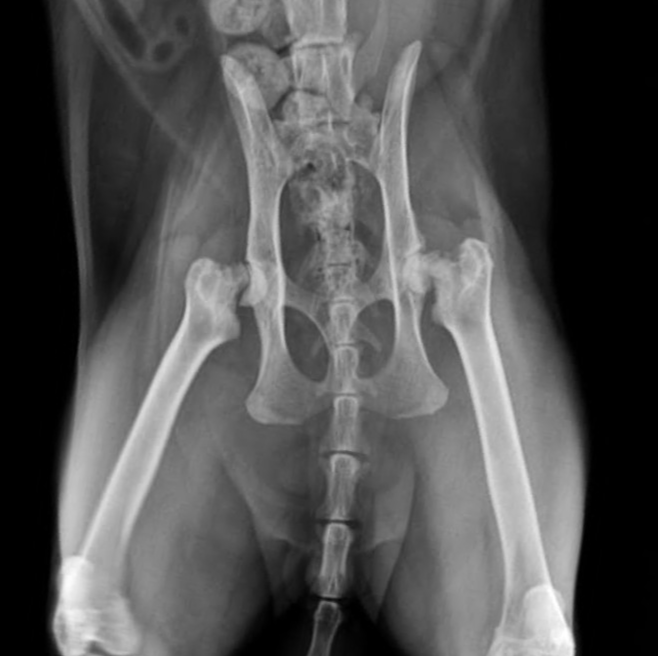

egg–Calvé–Perthes disease (LCPD) is a non-inflammatory, degenerative orthopedic disorder characterized by avascular necrosis (loss of blood supply) to the femoral head

As blood flow to the capital femoral epiphysis becomes compromised, the bone undergoes ischemic necrosis, collapse, and eventual deformation, leading to joint incongruity, pain, and lameness

Bilateral FHO was recommended starting with the most affected limb and the other to be scheduled after 3 months